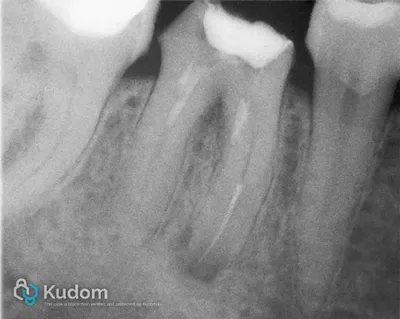

Trattamento endodontico di un primo molare mascellare, con attenzione alla corretta detersione, sagomatura e otturazione.